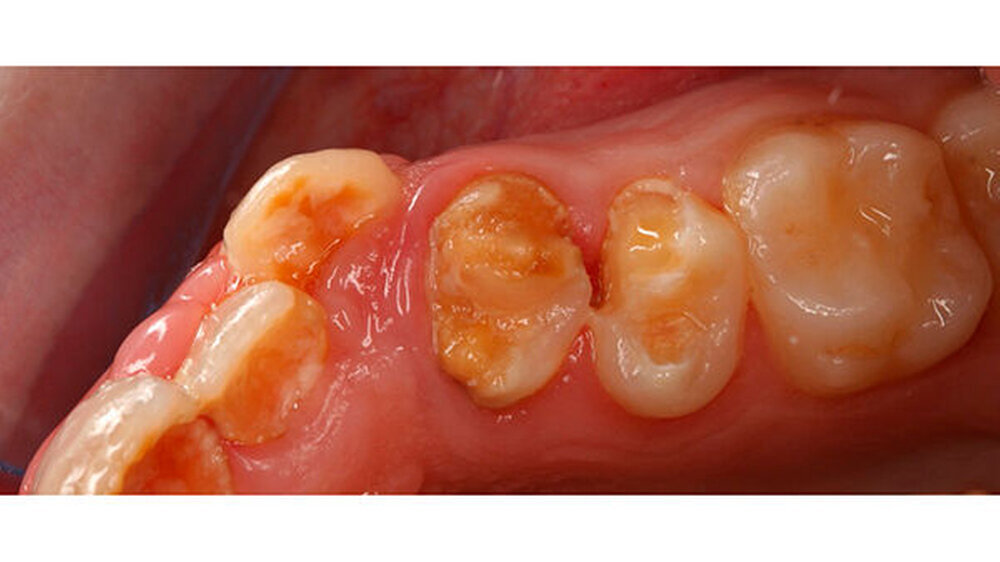

Das klinische Bild der MIH reicht von einem bis zu vier betroffenen Molaren, nur selten sind alle Zähne in ähnlicher Ausprägung geschädigt [Weerheijm et al., 2001]. Die bleibenden Frontzähne können ebenfalls betroffen sein, diese weisen allerdings in der Regel keinen Schmelzeinbruch auf und sind selten bis gar nicht überempfindlich [Weerheijm et al., 2001] (Abbildung 2).

Bisher wurde nicht beschrieben, dass die Frontzähne nur allein betroffen sein könnten. Meist wird - wenn die Frontzähne zusätzlich zu den Molaren betroffen sind - über mangelnde Ästhetik geklagt und die Kinder aufgrund ihres Aussehens gehänselt.

In schwerwiegenden Fällen kann der Einsatz eines Komposits das beste Ergebnis erzielen (Abbildungen 2, 13 und 14)